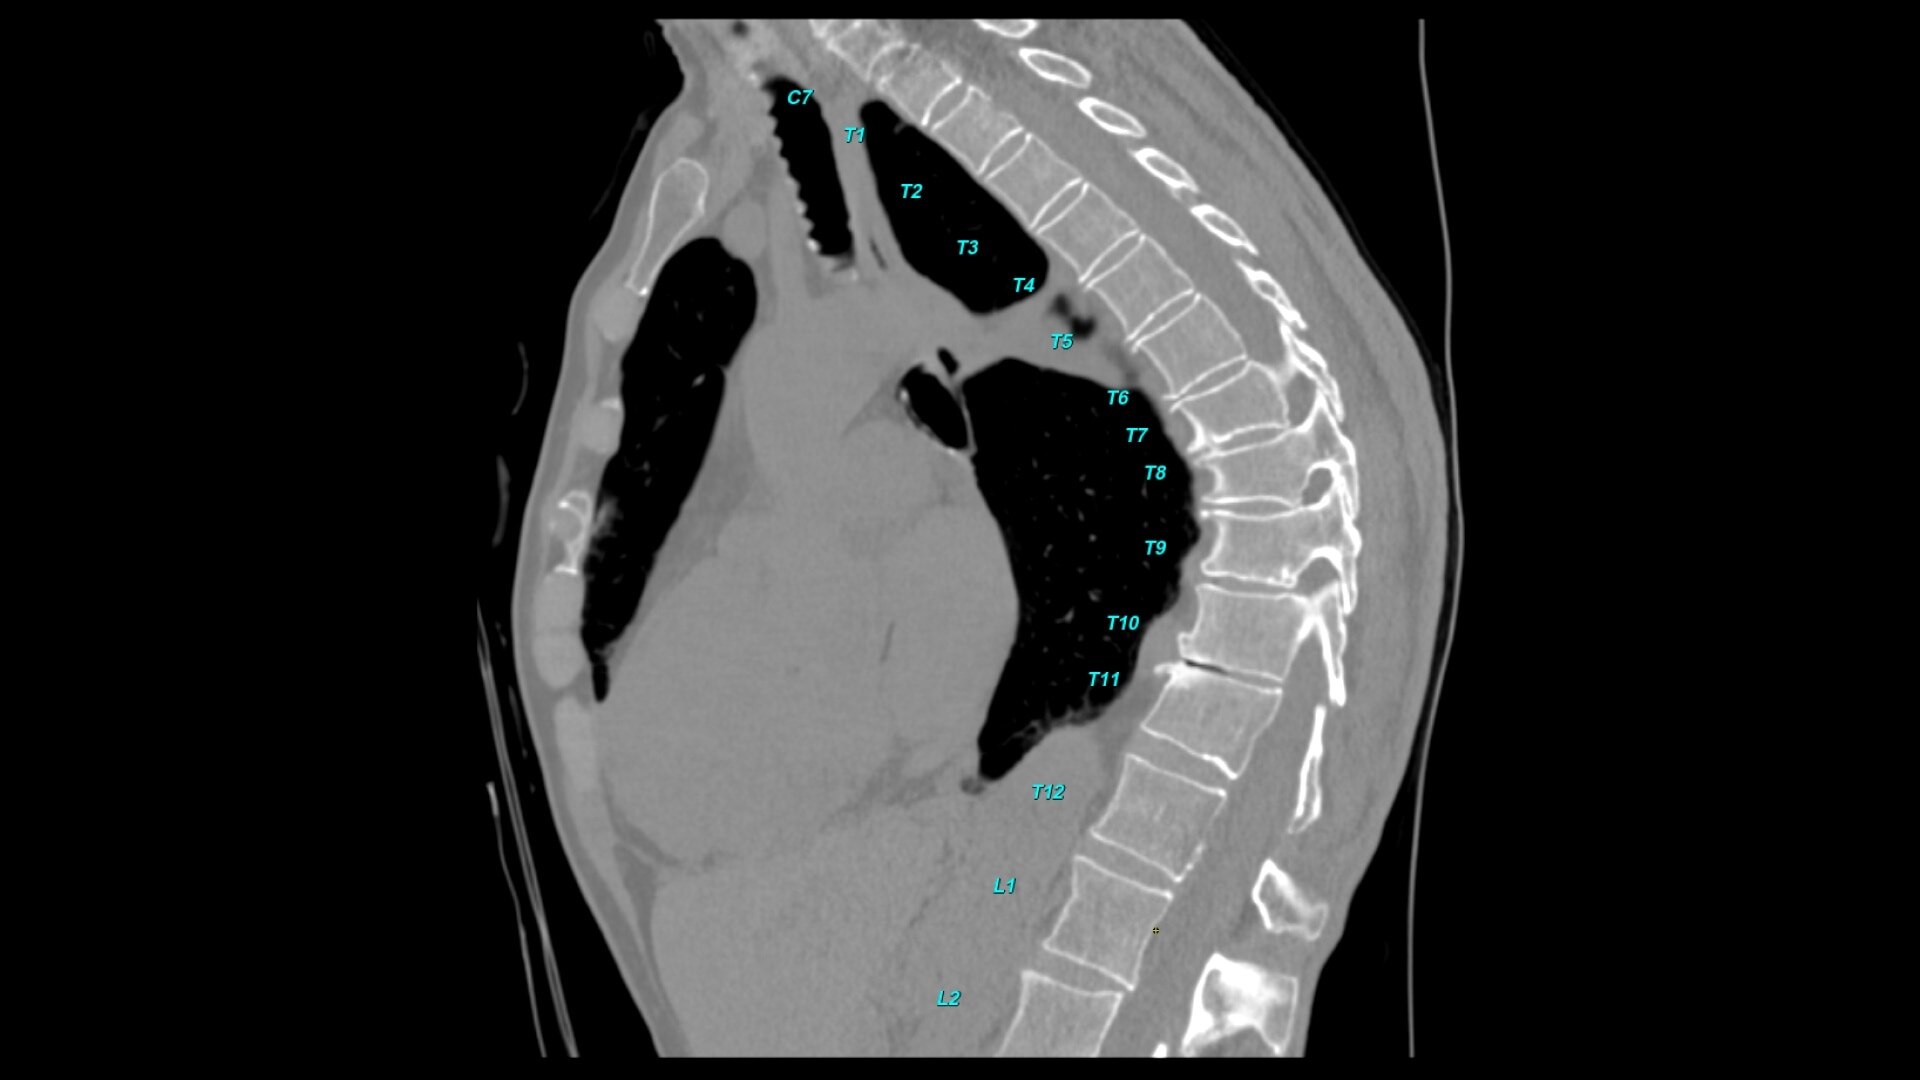

Bone VCAR

Spine assessment with deep-learning based CT application.

Automated spine identification and labelling.

>90% labeling accuracy based on Deep learning algorithm trained on global datasets acquired with a broad range of acquisition parameters.

• Automated spine labeling

• Works on full spine acquisitions as well as limited acquisitions containing segments of the spine